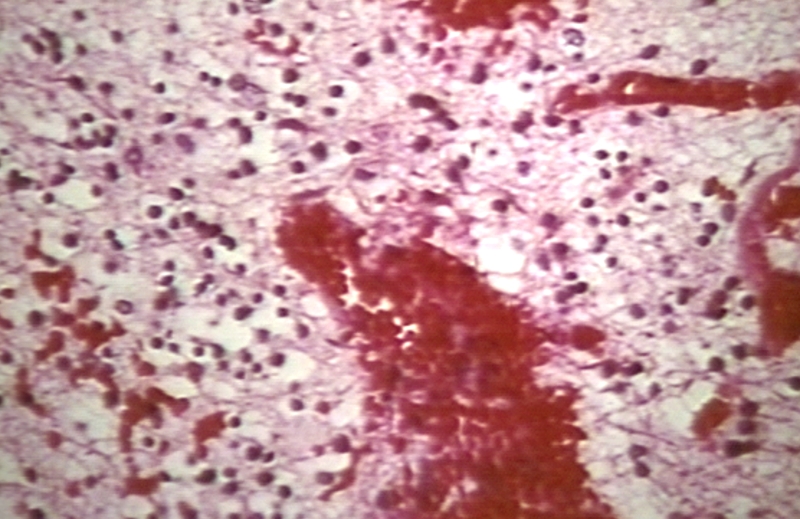

HISTOLOGY: NERVOUS: BRAIN: ANENCEPHALY, AREA CEREBROVASCULOSA